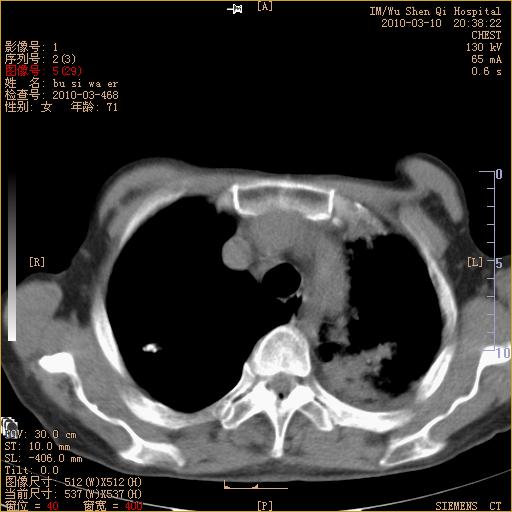

以下是引用随光逐影在2010-3-11 0:41:00的发言:[br]1)考虑左肺及右肺上叶继发性肺结核并左肺炎症感染。2)左侧支气管内膜结核可能;建议必要时行纤支镜检查。3)肺气肿。4)心包膜增厚(或少量心包积液)。5)左侧胸腔积液。